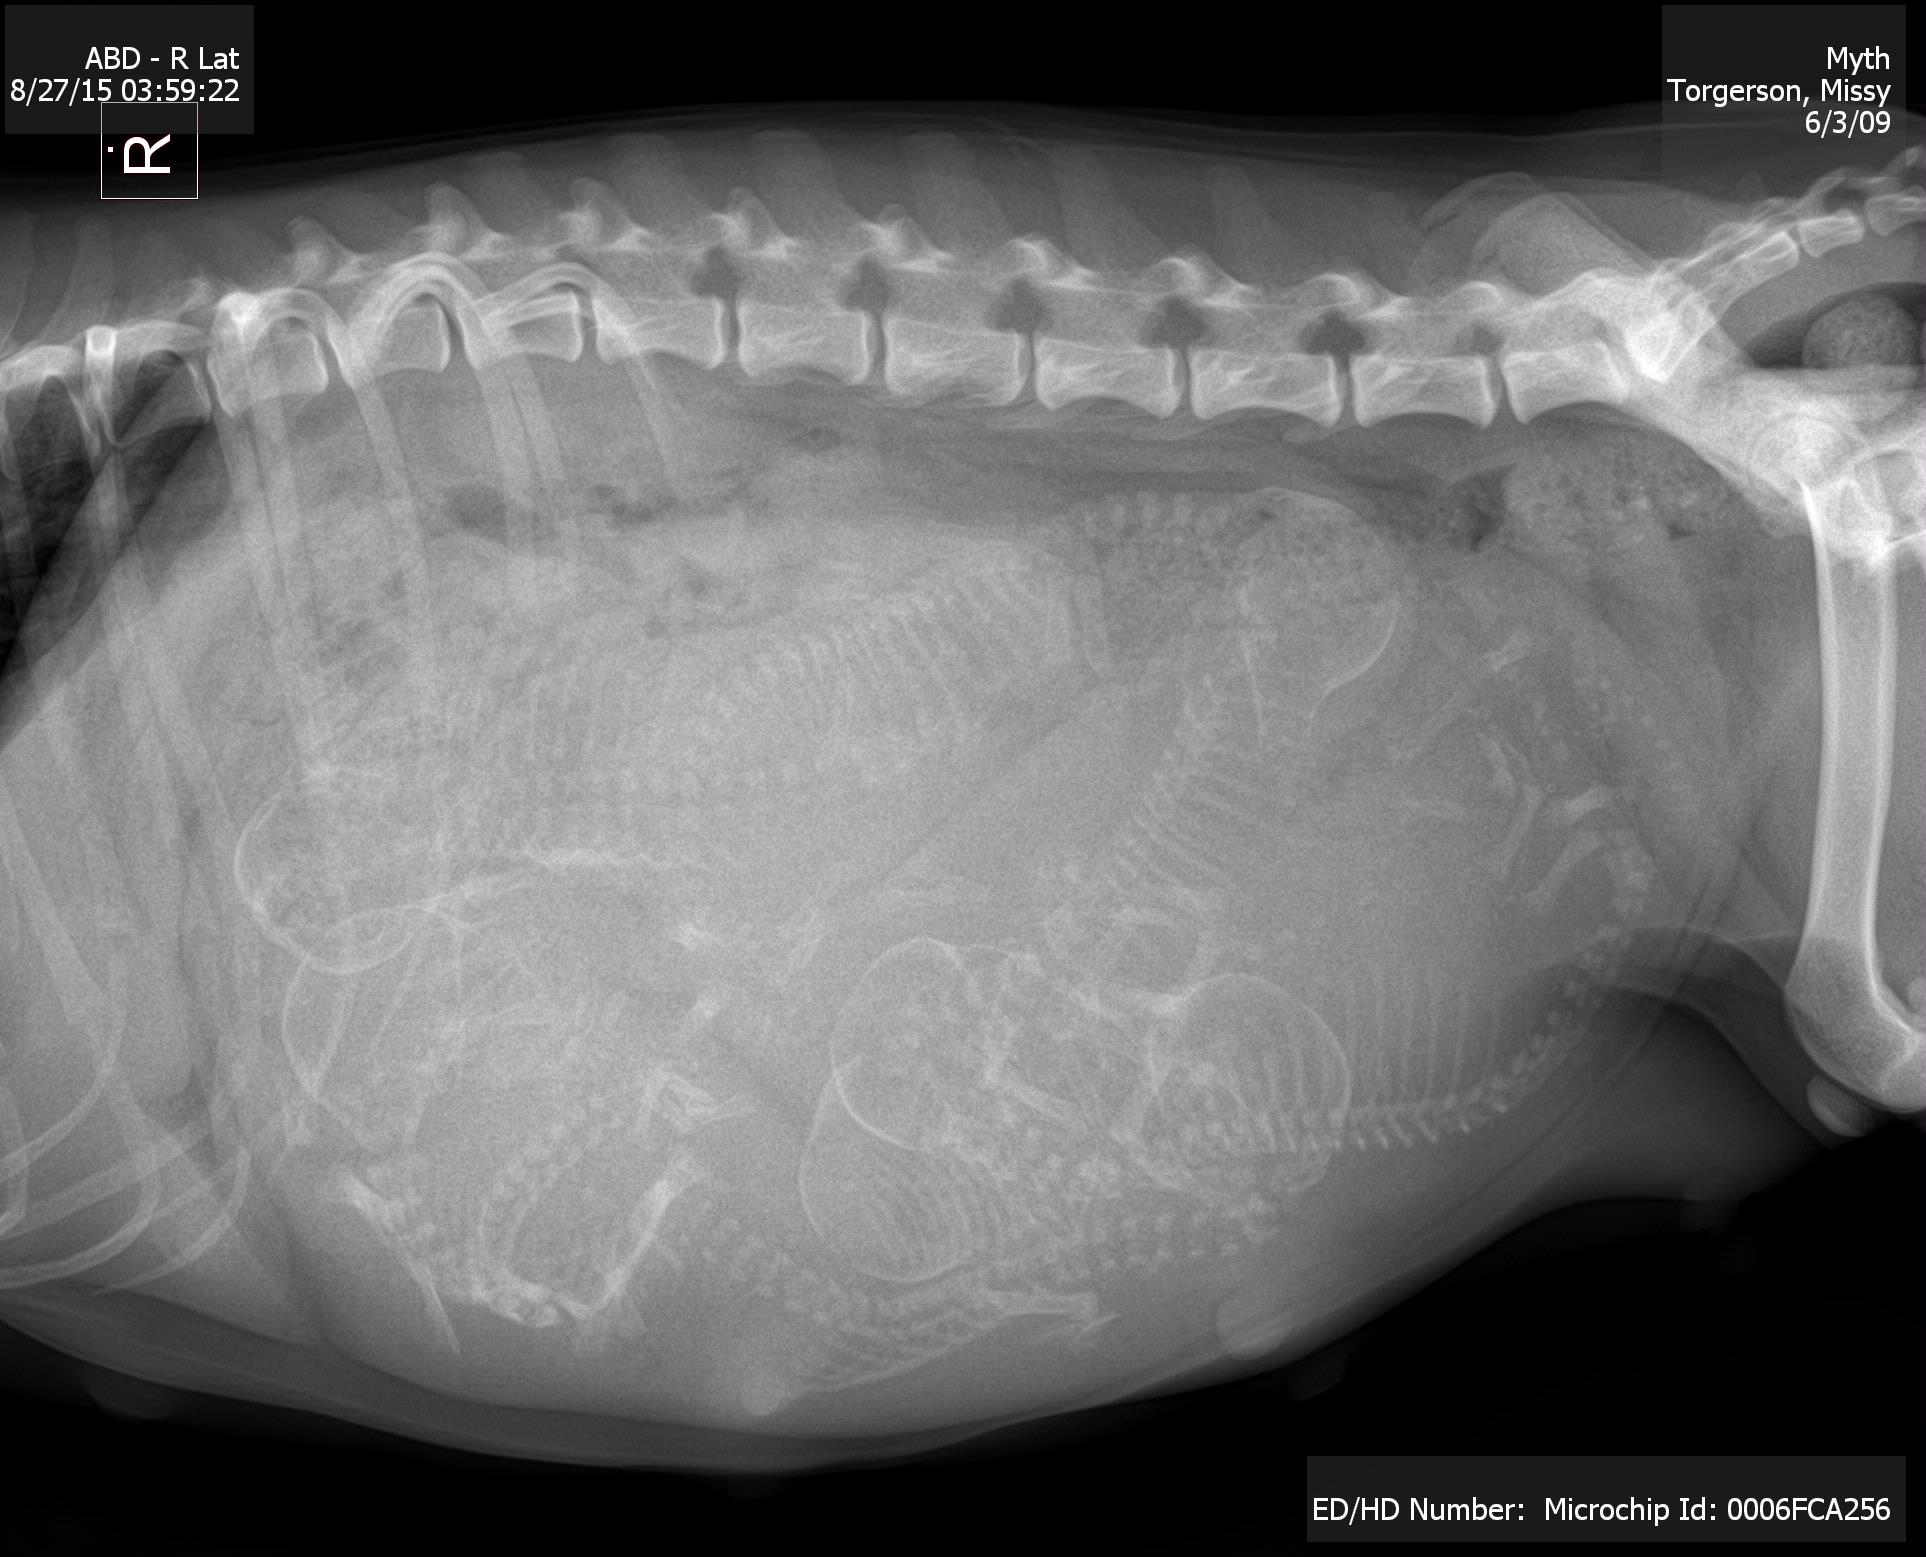

Posted: September 2, 2015 Filed under: Apso Aficionados 7 CommentsSunday morning this bellyful of puppies arrived…

Six puppies. Three boys and three girls!